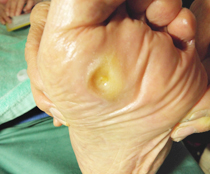

母趾種子骨炎

足裏の親指の付け根の部分が痛みます

母趾種子骨に体重が集中しています

母趾種子骨炎の治療

足に合わせた中敷き